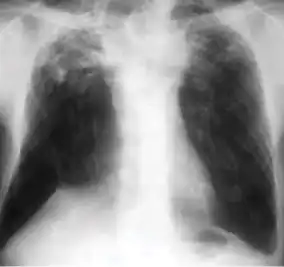

Dense homogenous opacity in right, middle and lower lobe of primary pulmonary TB. -

Chest x-ray showing patchy opacification on the upper right and mid-zone lung with fibrotic shadows, as well as bilateral hilar lymphadenopathy. -